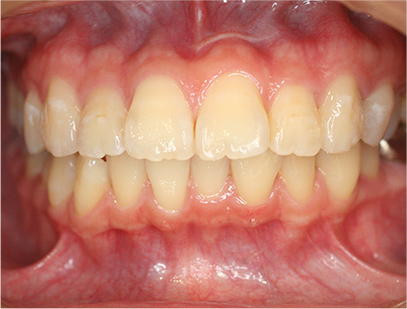

• 正面